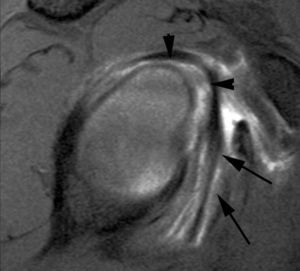

Lesiones por pinzamiento posterosuperior (posterosuperior impingement syndrome) < del LG superior con extensión posterior (SLAP tipo II-b), roturas parciales o completas del tendón del supraespinoso y pequeñas fracturas por compresión del margen posterosuperior del trocánter. Estas lesiones se producen típicamente en el atleta lanzador.

La etiología y el mecanismo de producción de estas lesiones han sido ampliamente debatidos. Jobe et al en 198930 consideraron que estas lesiones eran debidas a una laxitud de la cápsula anterior que producía una migración anterior de la cabeza humeral durante la abducción y rotación externa. En 1991, Walsh et al31, siguiendo la teoría de Jobe et al30, describieron el síndrome de pinzamiento interno o posterosuperior relacionado con una laxitud capsuloligamentosa anterior. En 1998, Burkhart et al describieron una alta incidencia de SLAP II-b en el atleta lanzador32. Estos mismos autores llegaron a la conclusión en el año 200333 de que las lesiones descritas anteriormente son producidas por una cascada de eventos originados por una fibrosis y engrosamiento de la cápsula posteroinferior y de la banda posterior del LGHI. Según estos autores, el atleta lanzador, después de múltiples movimientos de abducción y rotación externa, consigue un desplazamiento del punto de rotación y del arco de traslación del trocánter desde el centro de la cavidad glenoidea hacia arriba y hacia atrás «la zona» tal como se describe anteriormente (microinestabilidad). Todo ello conduce a un engrosamiento de la cápsula posterior que evoluciona a una restricción de la rotación interna (fig. 34). A esta restricción se la considera el punto de origen de la cadena de lesiones que conducen a lo que se llama el «brazo muerto» (the dead arm) que representa el final de una carrera profesional deportiva. La restricción de la rotación interna se la conoce bajo las siglas de GIRD (glenohumeral internal rotation deficit). Sin embargo, no queda claro si la traslación posterosuperior del centro de rotación en el atleta sucede antes o después de la formación de cicatriz y engrosamiento capsular posterior.

Cuando el deportista consigue crear, a través del entrenamiento, este desplazamiento posterosuperior del centro de traslación o bien tiene lugar a través del engrosamiento de la cápsula posteroinferior, el hombro llega a conseguir una rotación externa de más de 150 grados en abducción a 90 grados. En este momento se llega a un punto crítico, en el cual la tensión que se produce a nivel de la inserción del TLB, en el borde superior del LG, conduce a un «arrancamiento» del mismo, con extensión de la lesión hacia la parte posterior (SLAP II-b); a este mecanismo se le conoce como peel back (fig. 35).

Una vez que se ha producido la lesión SLAP II-b, la continuación de las fuerzas de extrema rotación externa conducen a una torsión repetitiva del tendón supraespinoso, que lleva a una rotura parcial o completa del mismo (fig. 36).